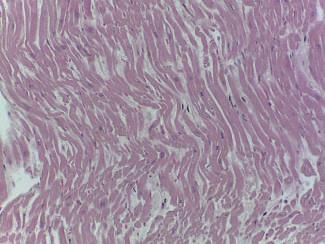

A formação dos livores cadavéricos também ocorre ao nível do hábito interno, com acumulação de sangue nas zonas dependentes dos órgãos. É bastante evidente nos pulmões, com uma diferença marcada da coloração entre a metade anterior e posterior do órgão nos cadáveres em decúbito dorsal e na distribuição do edema e congestão. No cora ção pode ser visível uma área mais escura, interessando a parede posterior do ventrículo esquerdo, que não deve ser confundida com uma isquemia do miocárdio. Também é possível observar uma alteração da coloração no intesti no delgado que se pode diferenciar de enfarte mesentérico pela sua distribuição não contínua.